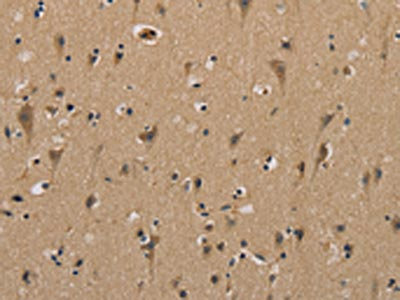

The image on the left is immunohistochemistry of paraffin-embedded Human brain tissue using CSB-PA274859(MYL3 Antibody) at dilution 1/40, on the right is treated with fusion protein. (Original magnification: ×200)